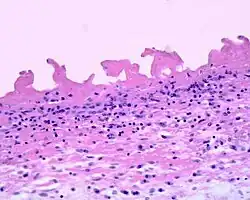

| Pericarditis fibrinosa | |

Fibrinous pericarditis is an exudative inflammation. The pericardium is infiltrated by the fibrinous exudate. This consists of fibrin strands and leukocytes. Fibrin describes an amorphous, eosinophilic (pink) network. Leukocytes (white blood cells; mainly neutrophils) are found within the fibrin deposits and intrapericardic. Vascular congestion is also present. Inflammatory cells do not penetrate the myocardium (as is seen with other presentations of pericarditis), and as a result, this particular variant does not present with diffuse ST elevation on ECG (a classic sign of pericarditis known as stage I ECG changes which are seen with other causes)[1] because the inflammatory cells do not penetrate the myocardium. To naked eye examination, this pathology is referred to as having a "Bread and Butter Appearance".